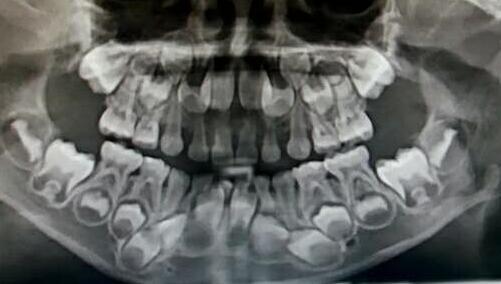

小孩牙齿x光图,小孩牙齿图片恒牙图片

看牙齿的x光片如何看出牙齿是恒牙还是乳牙?

没换牙的小孩的x光图

正常儿童牙齿x光图

儿童换牙x光图

小孩要换哪些牙齿图

小孩换牙齿的年龄图